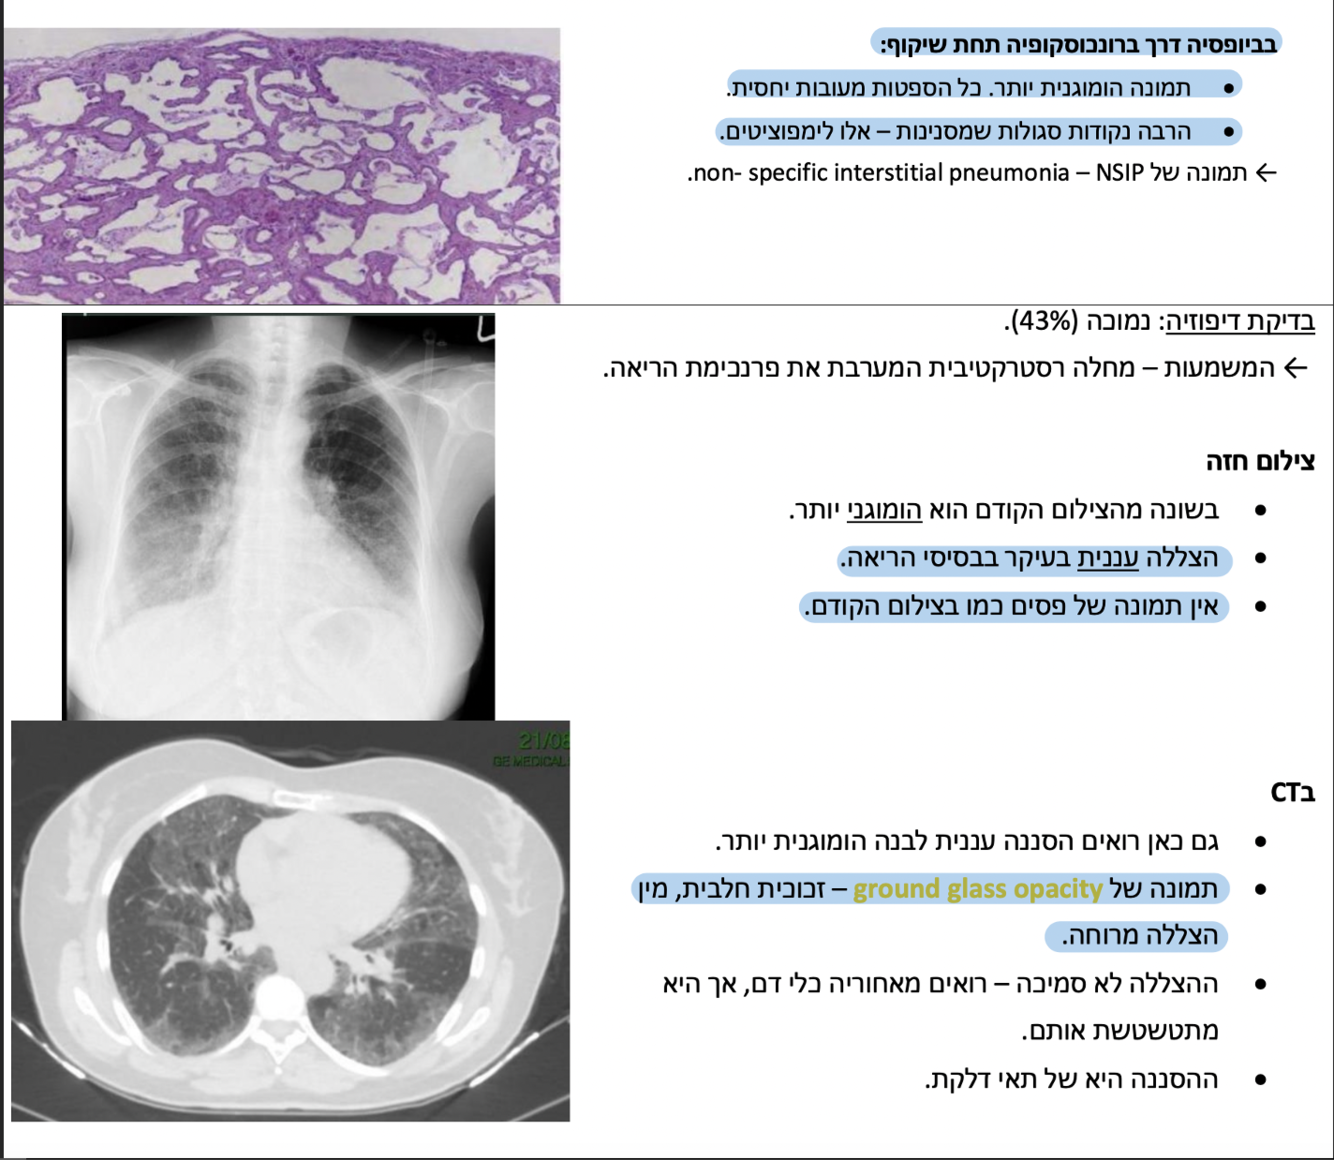

)non specific interstitial Pneumonia( NSIP מה המאפיינים של?

בצעירים, נשים, לא מעשנים.

Ground glass בסיטי יהיה מראה של

בתפקודי נשימה רואים עדות למחלה רסטרקטיבית בפרנכימת הריאה ולאחר מכן ניתן לקחת ביופסיה ע״י

BAL שטיפה אלוואולרית

סיווג:

טיפול- הרחקת הגורם האלרגני, סטרואידים, במחלה פיברוטית- טיפול אנטיפיברוטי.